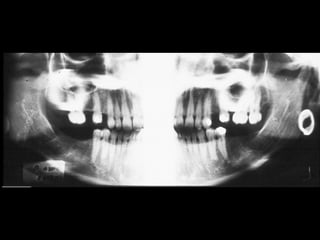

Hình ảnh ma

Bóng của vật thể cản quang

nằm bên đối diện (khuyên tai,

cấu trúc giải phẫu nào đó)

Đặc điểm của hình ảnh ma:

 Nằm bên đối diện

 Cùng hình dạng

 Phóng to hơn

 Nằm cao hơn

 Mờ hơn

Hình ảnh ma của khuyên tai

15 2

Máy trợ thính (mũi tên đỏ) có hình ảnh ma (mũi tên xanh).